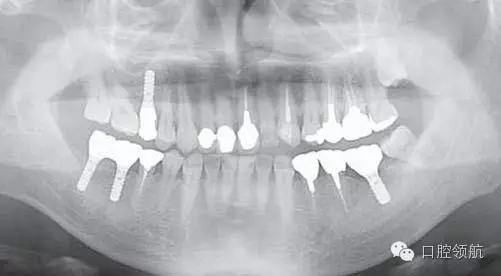

圖2是右側種植體植入后,左下磨牙缺損部診斷用導板戴用時的曲面斷層影像。拔牙后6個月,在預定植入部位有若干不透明的影像。

圖2 左下磨牙缺損部植入前的曲面斷層影像。